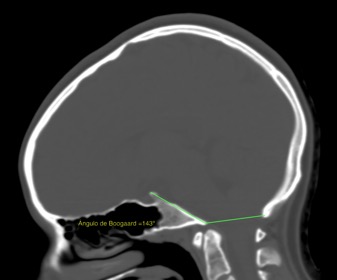

Platybasie (PTB) ist eine Anomalie des Schädelknochens, die in einer Abflachung der Schädelbasis besteht. Sie führt zu einer Öffnung des basalen Boogard-Winkels. Der Normalwert dieses Winkels liegt zwischen 115º und 140º. Wenn dieser Winkel mehr als 140º beträgt, spricht man von Platybasie. Zur Feststellung einer Platybasie können auch andere Bezugswinkel herangezogen werden, z. B. der Bull’sche Winkel (Normalwert 13º).

Zur Diagnose und Verlaufskontrolle der Platybasie wird der Schädel mit einer Computertomographie – Schädel-CT – untersucht.

Abb. 1 Platybasie, gesehen durch einen CT-Scan.